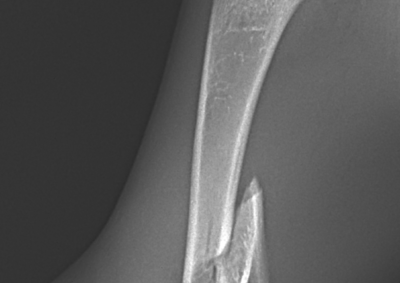

整形外科 注意 ボタンをクリックした先に、治療中および手術中の画像が説明で使用されている場合がございます。 そのような画像に弱い方は閲覧なさらないようお願いいたします。 整形外科 股関節脱臼に対するBUSTOR #65 整形外科 若齢犬の脛骨骨折 整形外科 橈尺骨固定術 #259 整形外科 膝蓋骨内方脱臼 G4 整形外科 膝蓋骨内方脱臼 G2~3 整形外科 橈骨固定術 #258 整形外科 膝蓋骨内方脱臼G3 整形外科 MPL G2 整形外科 CBLO #241 整形外科 膝蓋骨内方脱臼G3 整形外科 LCPDに対するFHNE 整形外科 CBLO#240 × Piezosurgery <12345678> 症例カテゴリー 放射線治療整形外科軟部組織外科脳神経外科内科腫瘍外科救急・集中治療リハビリテーション科腫瘍内科内視鏡科脳神経科呼吸器外科中医・漢方猫の腎移植循環器科